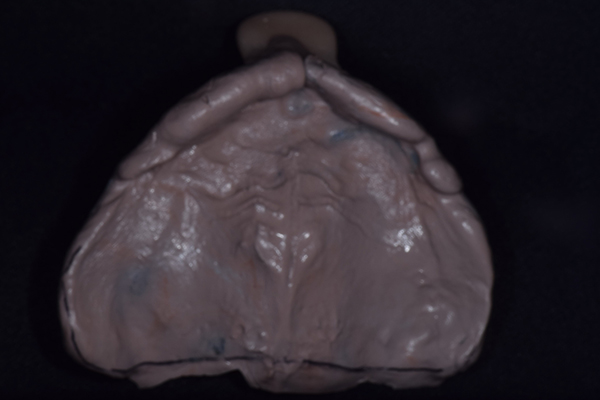

上の入れ歯(表)

上の入れ歯(裏)

入れ歯は極力薄くするために金属を使用しました。しっかり噛める様にするため、ノンメタルクラスプデンチャーにはしませんでした。

右上と左下の歯がない方です。 上の入れ歯の安定が悪く、作り直したいとのことでいらっしゃいました。 今お使いの上の入れ歯を見てみると、口蓋部分が抜けており、安定性に欠ける構造になっていました。この入れ歯はノンメタルクラスプデンチャーといって、金属のバネを使用しない 入れ歯になります。これは見た目は良いのですが、歯への負担が大きいことと、入れ歯自体がやわらかいため、噛むには不便なことがあります。